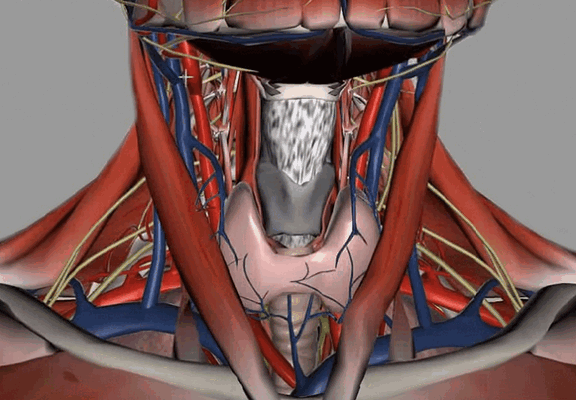

- Это немного разные вещи. МРТ шейного отдела позвоночника - узконаправленное обследование. При выполнении данной процедуры видны только позвоночник и спинной мозг. МРТ мягких тканей шеи - обследование более расширенное. При его проведении просматриваются и оцениваются мышцы, слюнные железы (подъязычная, нижнечелюстная, околоушная), щитовидная железа, пищевод, гортань, а также межфасциальные пространства. Просматривается также корень языка, грушевидные синусы, лимфоузлы, парафарингеальные (окологлоточные) области. Позвоночник и спинной мозг на МРТ шеи тоже видны, но не так детально, как на МРТ шейного отдела позвоночника.

Анатомия шеи

Внутренние структуры зоны интереса

Анатомическая область включает межфасциальные пространства:

пред- и позадиорганное;

Наибольший интерес представляет висцеральное пространство, включающее органы шеи:

глотку с верхней частью пищевода;

гортань и трахею;

пара- и щитовидную железы;

возвратный гортанный нерв.